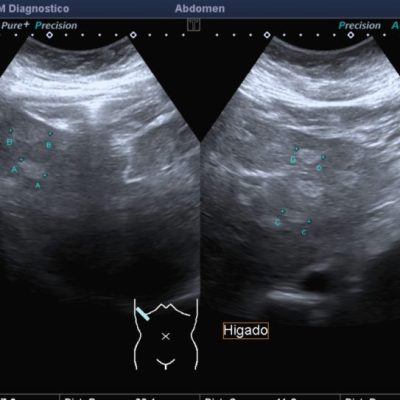

El médico de referencia le indica nueva ecografía de control, donde se observan múltiples y extensas lesiones focales hepáticas hiperecogénicas, redondeadas y confluentes, las cuales predominan en adyacencia a venas supra hepáticas, sin condicionar efecto de masa y sin alteración de la superficie hepática(fig. 1 y 2). Ante la valoración con Doppler color no presenta patrón de flujo peri ni intralesional y respeta el calibre de las venas supra hepáticas(fig. 3 y 4). Dada las características ecográficas se sospecha esteatosis focal multinodular confluente como principal diagnóstico presuntivo, siendo los diagnósticos diferenciales patologías de naturaleza infecciosa, tumoral o metastásica.

El examen radiológico abdominal más comúnmente utilizado en prevención es la ecografía (US) dado que es un método económico y accesible, no invasivo y que no utiliza rayos X, con el cual se logra fácilmente el diagnóstico de esteatosis, dado que se reconoce aumento difuso de ecogenicidad del parénquima hepático. Los criterios principales: la ecogenicidad del parénquima hepático debe ser mayor que la de la corteza renal, mala definición diafragmática, de los vasos supra hepáticos y de la arquitectura intra hepática.2(fig. 8, 9a y 9b)